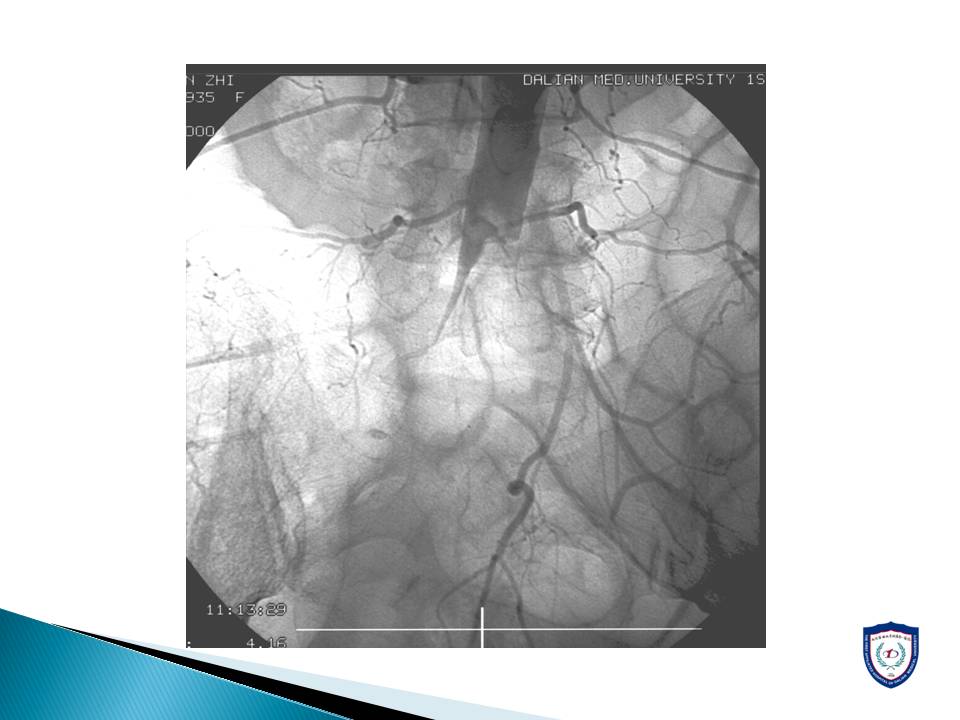

心房颤动导致的脑卒中和外周动脉栓塞的介入治疗